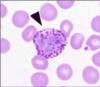

Eosinophil